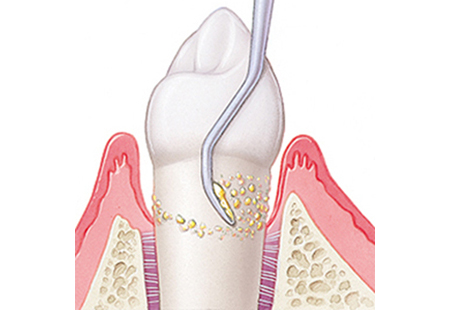

ルートプレーニング(歯ぐきの中の清掃)

歯ぐきの奥深く(歯周ポケット内)に隠れた歯石や、毒素に汚染された歯根の表面を滑らかにする処置です。

ここをツルツルに整えることで、細菌の再付着を防ぎ、歯ぐきが歯に再び密着するのを助けます。